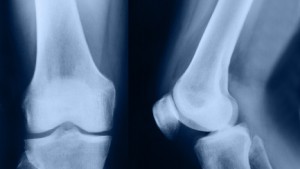

Our bones are made up of lots of different minerals and proteins, with two recently coming to the attention of scientists at the university. They discovered than when our bones are under stress, proteins osteopontin and osteocalcin divided to create a tiny hole. This helps our structure cope with forces and makes bones stronger, showing that the molecules are important for our wellbeing. This process is widely known as dilatational band formation, although until now scientists have been unsure of the important part osteocalcin plays in this natural defence system. The research suggests that if we lack these minerals instead of dividing in this way, there is a complete break and we fracture our bones. Breakages are more likely to happen to us if we suffer from a condition like osteoporosis, so knowing why fractures happen in the first place could teach us how to change our lifestyles to prevent them.